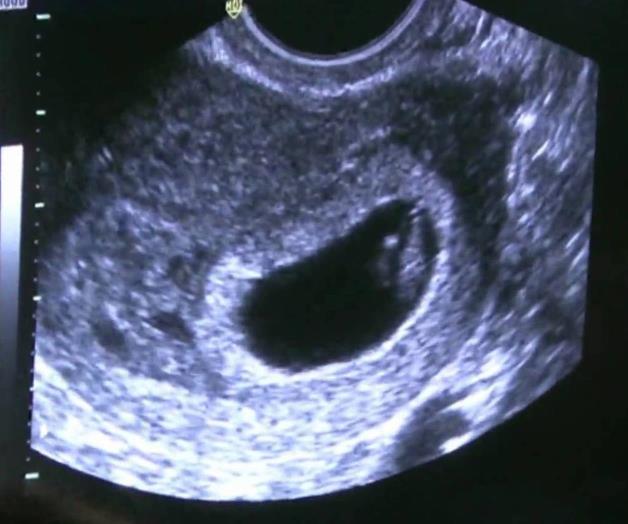

EXAMEN. Estudiantes de The College of Health Care Professions ofrececieron sonogranas sin costo alguno.

McAllen, Tx.- Como parte de su preparación para ser profesionales de la salud, estudiantes del Colegio de Profesionales de la Salud proporcionaron sonogramas gratuitos para las mujeres en cualquier etapa del embarazo.